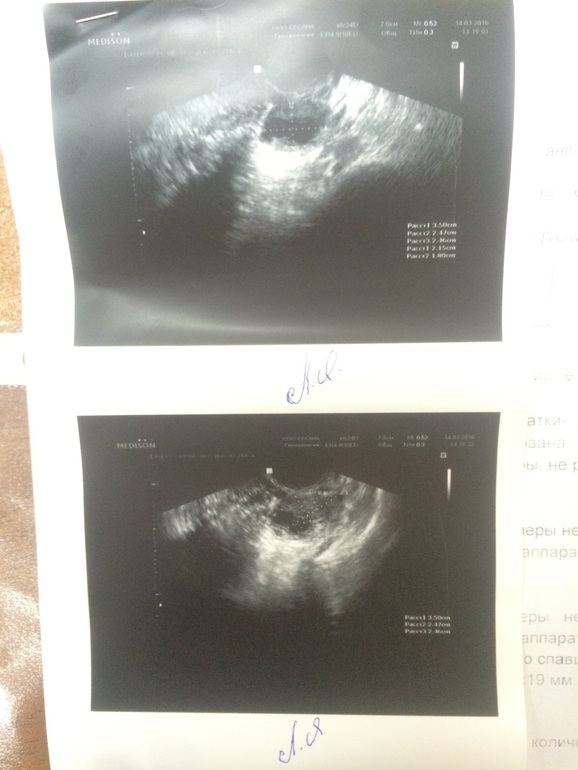

Сходила сегодня (в продолжение моих печалек отрицательный тест) на узи (14 дц) иииии...... (под кат)

Там ЖТ 21*18

это первое фото ЖТ в моем дневнике (аппарат узи совсем не хороший поэтому на фото плохо видно, но мне на экране показали его хорошо) моей радости небыло предела. Эндик 9,7 (в хвасте 4,9 мм)

Да жидкость есть )) на экране она мне показала все рассказала ... там ЖТ прям как на картинке, я такого никогда в живую не видела ))) она сказала добавить дюф, т.к. ее немного смущает мой эндометрий )) вообщем сказала приходить после задержки )) очень жду и верю )